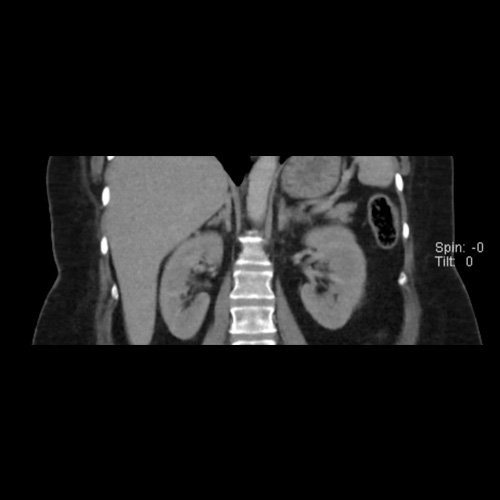

• Tomografía de abdomen y pelvis sin contraste oral con contraste EV (12/02/26):  El hígado es de forma, tamaño y situación habituales. Su superficie es lisa, y sus bordes son agudos. Imagen hipovascular aislada de 15 mm en segmento V de aspecto inespecífico. Sugiero complementar con RMI. La vía biliar intra y extrahepática es de calibre conservado. La vesícula biliar es de forma, tamaño y situación normales, sin imágenes que sugieran la presencia de litiasis. Tener en cuenta que este método puede pasar por alto litiasis colesterínicas. El bazo es de forma, tamaño y situación normales. El páncreas es de características normales. El conducto de Wirsung es de calibre conservado. Adenoma adrenal izquierdo de 16 mm. Ambos riñones son de forma, tamaño y situación habituales. Concentran y eliminan adecuadamente la sustancia de contraste. Sin evidencia de alteraciones calicopiélicas ni ureterales. La aorta, las arterias ilíacas primitivas, internas, externas y femorales, son de calibre y trayecto conservado, permeables. La vena cava inferior y las venas ilíacas primitivas, internas, externas y femorales son de calibre y trayectoria conservados, permeables. No se observan adenomegalias intraperitoneales, retroperitoneales, ilíacas ni inguinales. No se observan alteraciones a nivel del tracto gastrointestinal. La vejiga es de paredes lisas, sin presentar efectos de masa endoluminales ni parietales. Utero en AVF, lateralizado a izquierda. Pequeña hernia umbilical de contenido graso y escaso líquido intrasacro. No se identifican alteraciones en las estructuras óseas visualizadas.

TC de abdomen y pelvis con contraste endovenoso (12/02/2026) Corte axial: adenoma adrenal izquierdo de 16 mm.

TC de abdomen y pelvis con contraste endovenoso (12/02/2026) Corte coronal: adenoma adrenal izquierdo de 16 mm.